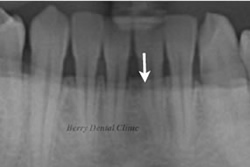

治療にて削る前、歯を抜く前、などに具体的に患者さんのお口のお写真やレントゲン写真などを使ってパソコンのシュミレーションソフトを用いてカウンセリング致します。

治療前に治療後の画像等を具体的にみることができるため、患者様の治療方法を納得していただいてから安心して治療に入ることができます。